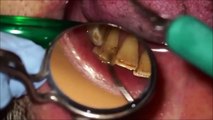

Learn The Benefits Of Dental Scaling With Our Dental Hygienist In Calgary

Our Dental Hygienist In Calgary, explains the process that a patient undergoes during dental scaling treatment. She also explains the several benefits associated with a dental scaling. Watch the video to learn more. #dentalhygienist #dentalhygienists #dentalhygienistincalgary #dentist #dentistry